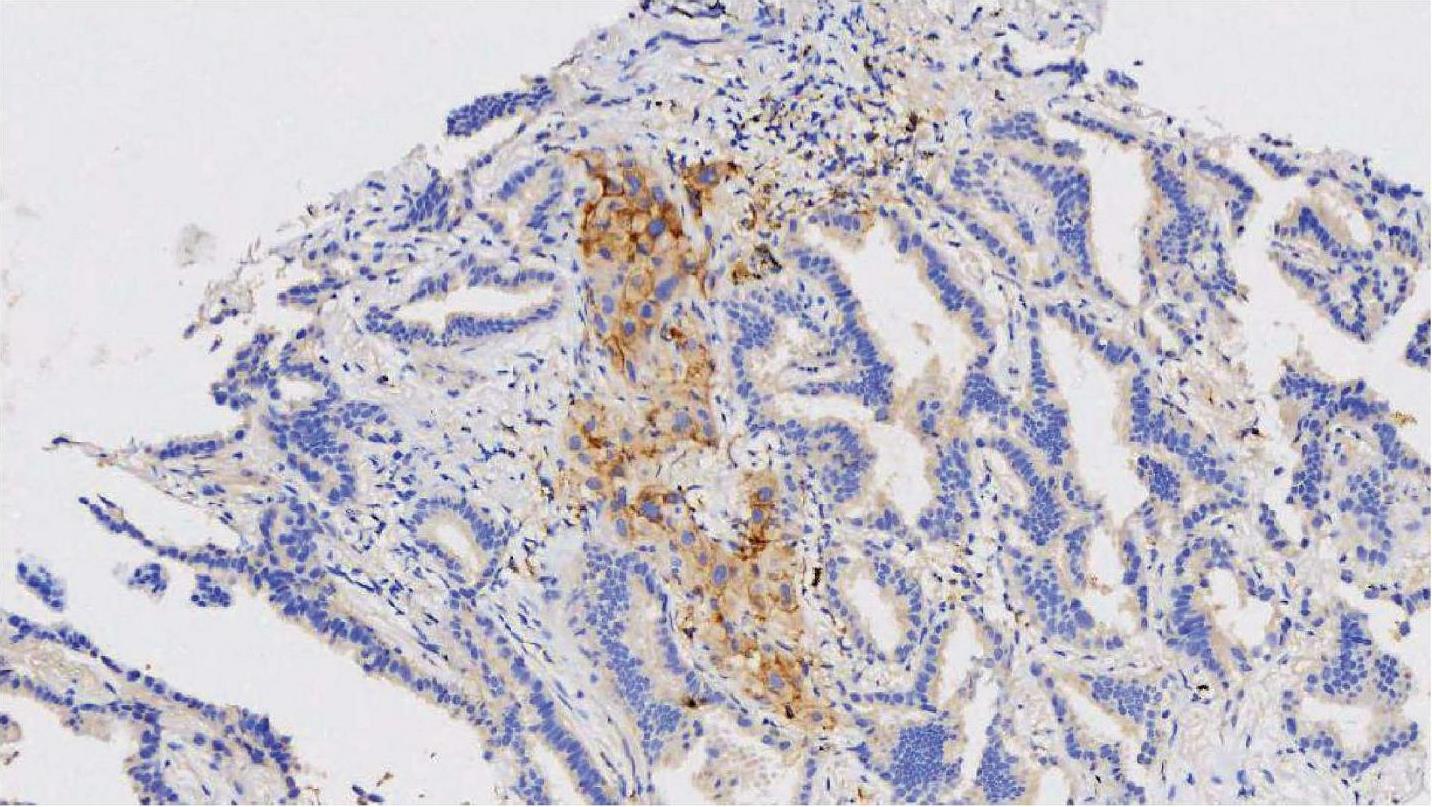

SP263克隆号检测平台及结果判读与22C3和28-8标准大致相同,判读结果以TC计算,不同的是若SP263仅有肿瘤细胞基底膜染色不能算作阳性,需基底膜及侧膜同时染色时才可判为阳性,根据肿瘤细胞PD-L1的表达分别为1%≤TC评分<5%、5%≤TC评分<10%、10%≤TC评分<50%、TC评分≥50%。图2-10和图2-11所示为肺浸润性腺癌HE染色图和PD-L1 (SP263)免疫组织化学染色图,图2-11显示肿瘤细胞基底膜及侧面均染色,应纳入PD-L1评估,TC评分≥50%。图2-12和图2-13所示为肺浸润性腺癌HE染色图和PD-L1 (SP263)免疫组织化学染色图,部分肿瘤基底膜及侧面均染色的肿瘤细胞(如黑色箭头所示),应纳入PD-L1百分比评估中,而染色的免疫细胞应排除PD-L1评估;部分肿瘤细胞仅基底膜染色,侧面未染色(如红色箭头所示),不应纳入阳性肿瘤细胞。不同TC评分的NSCLC PD-L1 (SP263)免疫组织化学染色结果如图2-14至图2-17所示。

图2-13 肺浸润性腺癌PD-L1 (SP263)免疫组织化学染色图(×400) [7]

注:部分肿瘤基底膜及侧面均染色的肿瘤细胞(如黑色箭头所示),应纳入PD-L1百分比评估中;部分肿瘤细胞仅基底膜染色,侧面未染色(如红色箭头所示),不应纳入阳性肿瘤细胞;染色的免疫细胞应排除PD-L1评估